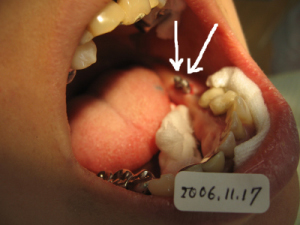

2本目を入れた状態。 このような方法で計4本入れます。 |